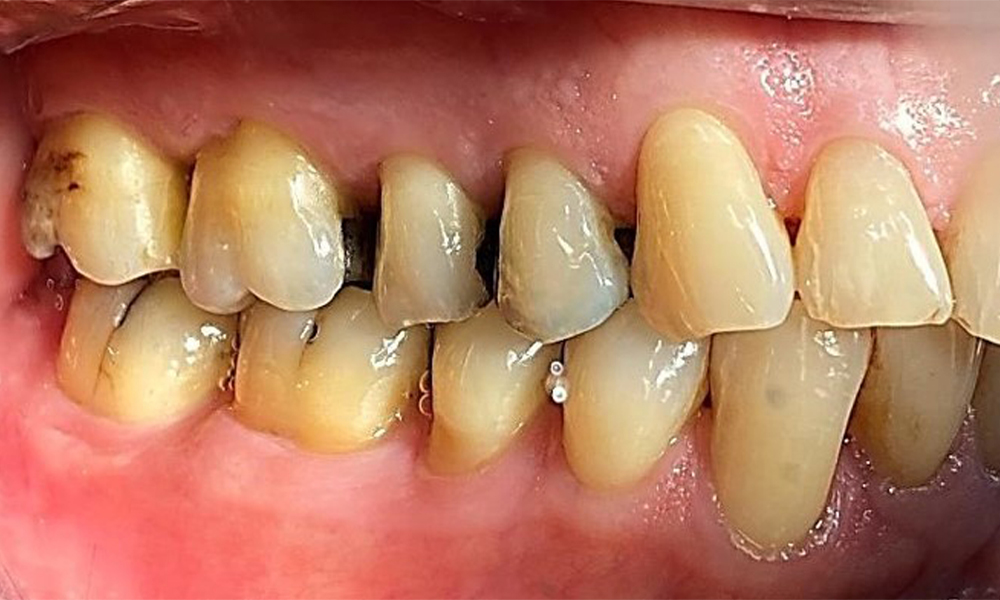

Right lateral view. Loss of the interdental papillae.

Fig. 3 Right lateral view. Loss of the interdental papillae. © Dr R. Krapf

The patient has a full dentition with 28 teeth, which includes amalgam and composite fillings in the molar and premolar regions. There is a visible clinical marginal gap present on tooth 14. Tooth 27 has an adequate gold inlay. There are also generalized attritions and abrasions. (Fig. 2, Fig. 3, Fig. 4, Fig. 5, Fig. 6)

The patient has stage II, grade B periodontitis (5). At 1 to 3 mm, the clinical probing depths were within the physiological range. Localized probing depths of 5 mm were observed on the mesiopalatal aspects on both 17 and 27. There are generalized recessions of 1–3 mm with partial loss of the interdental papillae (Fig. 2, Fig. 3, Fig. 4)